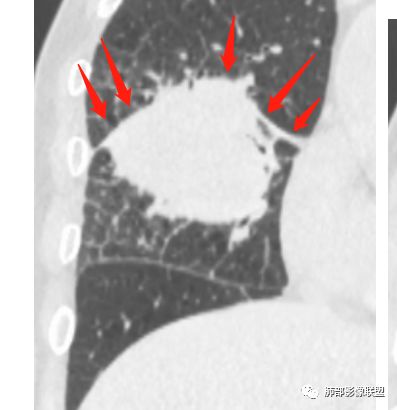

1.具有肉瘤的特性:肿瘤体积一般较大,直径约大于5cm,边缘清楚、光整,由于肿瘤生长迅速,可见大片坏死,坏死边界清楚;常见支气管推移。

2.具有癌些特性:如分叶、短毛刺、空洞,但是钙化及胸膜凹陷征少见,病灶往往是直接侵犯胸膜,可以远处转移,肺门及纵隔淋巴结可明显肿大;

3.强化方式:增强后病灶以环状强化为主,病灶周边多以癌组织为主,血供丰富,病灶中心区则以肉瘤成分为主,血供较差,易出现粘液样变性、坏死、出血,坏死边界清楚,所以增强CT对PSC与普通型肺癌有一定的鉴别价值。

1.本病例结合病理结果及影像综合分析,应该符合肉瘤样癌,上皮成分是腺癌为主;肿块的边缘毛刺、分叶及周围癌型淋巴管炎征象有符合腺癌的影像表现之处。

2.肿块巨大局部边缘膨隆、光整,坏死较彻底;明显跨叶生长(途经发育不全叶间裂或肺门,注意患者没有胸水),支气管阻塞伴推移等,这些更符合肉瘤的特性。

3.坏死区边界较清楚(皮囊样),环形强化明显,病灶内血管穿行等,都不符合我们常见的鳞癌。

4.肺肉瘤虽然也是肿块巨大,呈大片状坏死,但是边缘光整圆隆,没有分叶、毛刺征象,较少出现肺门及纵隔淋巴结转移。